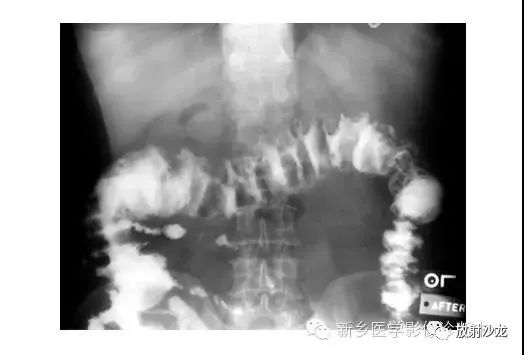

逆行通过肛管后所行X光片所示,证明了乙状结肠襻和正常肠道结构压力减低。

X线片表现出充满整个腹部的乙状结肠扭转。乙状结肠的两端可以理解成一个倒置的朝向骨盆的U型(图U)。在X光片直立位,可以看出气液平面(箭头)。咖啡豆的标志是乙状结肠扭转的典型的表现。充满气体的肠道包绕重叠水肿的肠壁所形成致密的白线,类似于一个咖啡豆。在这些X光片中,大肠的其余部分均不膨大,大概是因为扭转的点不造成阻塞,从而使消化产物可进入乙状结肠。